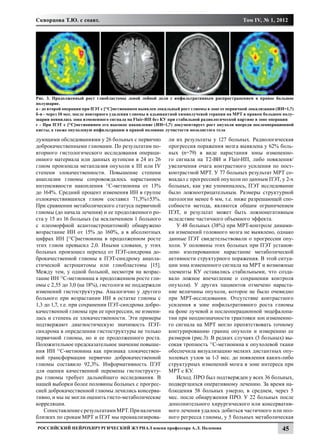

а 				                                    б.				                                      в.

Рис. 3. а - КТ поясничного отдела позвоночника. Отмечается более медиальное расположения фасеточного сустава на верхне-

поясничном уровне. На МРТ поясничного отдела позвоночника, в аксиальной проекции отмечена медиальная граница фасе-

точного сустава на уровне L1-L2 (б) и L5 -S1 (в). На уровне L1-L2 медиальная граница фасеточного сустава расположена более

медиально.